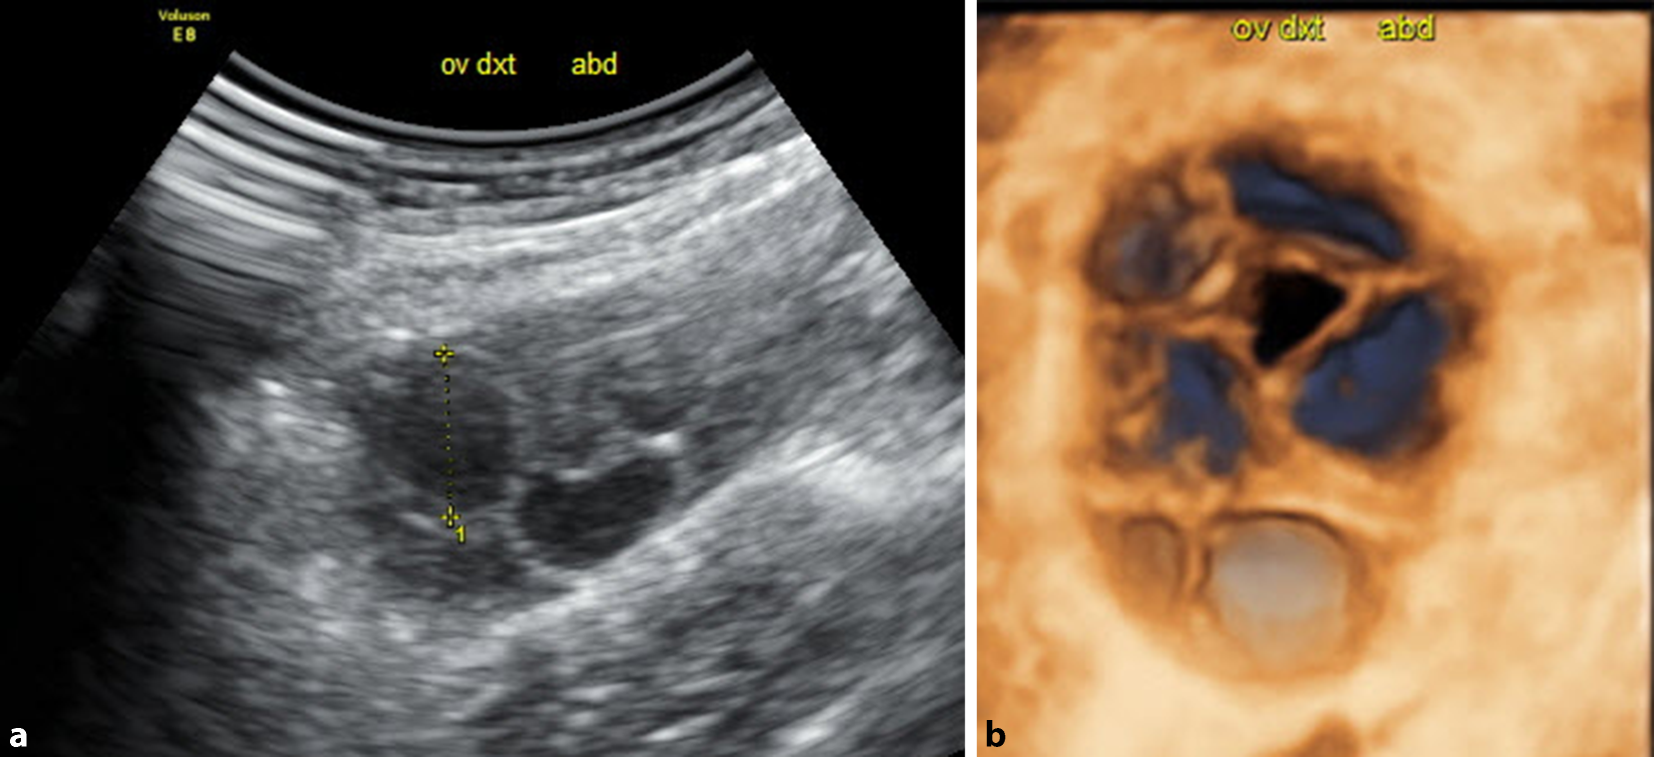

Lassen Sie das Potenzial Ihres Geräts nicht ungenutzt! Uterusfehlbildungen sind im B‑Mode nur mit großem Geschick, Erfahrung und Glück zu erkennen, während dies im 3‑D-Schall auch von abdominal meist rasch und einfach gelingt (Abb. 6). Auch bei der Differenzierung von Adnexzysten ist der 3‑D-Schall hilfreich (Abb. 7). In stimulierten Zyklen, wenn es um die Entscheidung geht, ob und wann die Ovulation medikamentös ausgelöst werden soll, ist zwar grundsätzlich der Vaginalschall zu bevorzugen, da er durch die kürzeren Abstände und meist höhere Auflösung wesentlich präziser ist. Kann aber nur der Abdominalschall zum Einsatz kommen, bringt die 3‑D-Funktion eine wertvolle Befunderweiterung und eine klinische Entscheidungshilfe (Abb. 8a, b).

Abb. 8

a Medikamentös stimuliertes Ovar am 12. Zyklustag mit einem 15 mm-Follikel von abdominal geschallt. b Die Anwendung des 3‑D-Schalls zeigt die im B‑Mode nicht so gut erkennbaren Follikel und hilft bei der Entscheidung, ob in diesem Zyklus eine Ovulation ausgelöst werden soll oder nicht